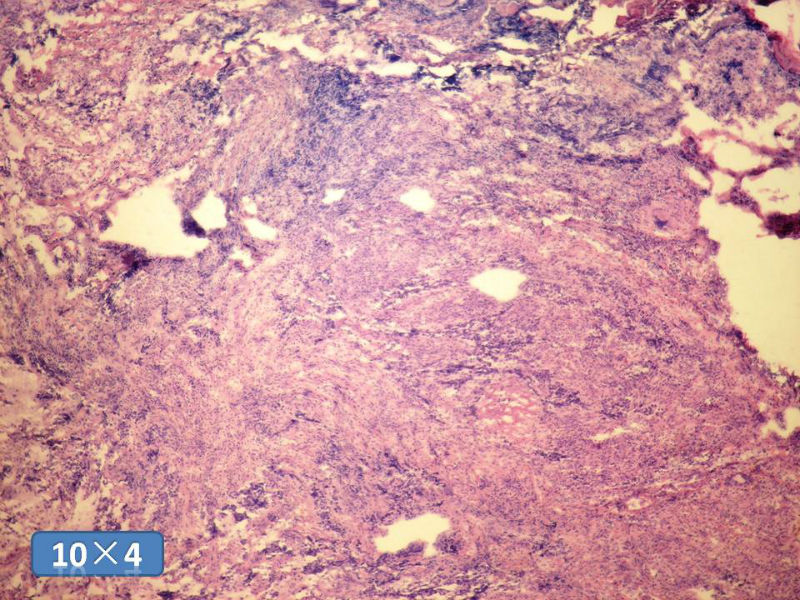

女性,50岁,乳腺肿物,冰冻切片(图1-25)

HE